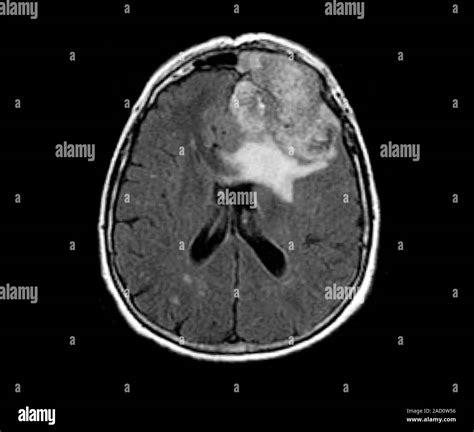

When a physician suspects an abnormality within the skull, a Brain Neoplasm MRI is the gold standard diagnostic tool used to visualize the intricate structures of the brain. Neoplasms, or abnormal tissue growths, can be benign or malignant, and magnetic resonance imaging (MRI) provides unparalleled detail to distinguish between these possibilities. By utilizing powerful magnets and radio waves rather than ionizing radiation, MRI technology produces high-resolution, cross-sectional images that allow radiologists and neurosurgeons to pinpoint the exact location, size, and characteristics of a potential tumor.

A standard Brain Neoplasm MRI protocol involves several different "sequences" or scan types. Each sequence is designed to highlight different biological features of the tissue. For example, T1-weighted images are excellent for anatomical detail, while T2-weighted and FLAIR (Fluid-Attenuated Inversion Recovery) images are highly sensitive to identifying edema or inflammation around a mass.

To improve the diagnostic accuracy, doctors often use a gadolinium-based contrast agent. When injected intravenously, this contrast material accumulates in areas where the blood-brain barrier is compromised, which is typical in many types of neoplasms. This "enhancement" helps doctors clearly delineate the tumor from healthy brain tissue.

These advanced tools provide the neurosurgeon with a "map" of the brain, identifying functional areas—such as speech or motor cortex—that need to be avoided during surgery. This level of precision is what makes the modern Brain Neoplasm MRI an indispensable tool in neuro-oncology.

Interpreting the Results